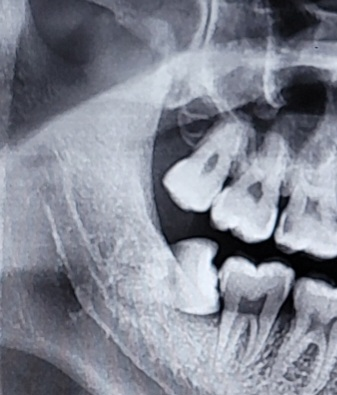

제 사랑니 ct사진인데 아래사랑니가 매복이고 신경이랑 가깝다고 얘기하시더라구요 뽑기 어려운편인가요? ㅜㅜ 대학병원가는게 나을까요?

아래 사랑니가 수평으로 누운 매복 사랑니이며 사랑니 뿌리끝이 밑으로 지나는 신경관과 접촉되어 있습니다.

이런 경우 사랑니 발치후 혀나 입술에 감각이상이 올 수 있습니만 대학병원에서 하나 구강외과 전문의가 진료하는 개인치과의원에서 하나 가능성은 서로 비슷합니다.

매복사랑니가 기울어져 있고 뿌리가 신경이 좀 가깝긴 하지만 난이도가 높은 발치는 아닙니다.